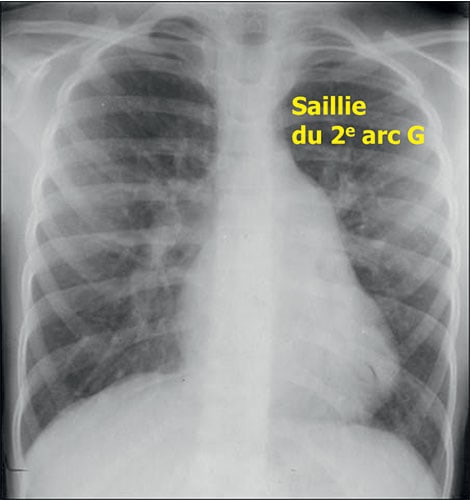

Fig. 11.7 ![]() Aspect typique de communication interatriale (CIA) de l’adulte au cliché de thorax de face.

Aspect typique de communication interatriale (CIA) de l’adulte au cliché de thorax de face.

Le cœur est peu augmenté de volume, avec une saillie de l’arc moyen gauche qui traduit la dilatation de l’artère pulmonaire due au shunt. Les poumons sont très hypervascularisés.